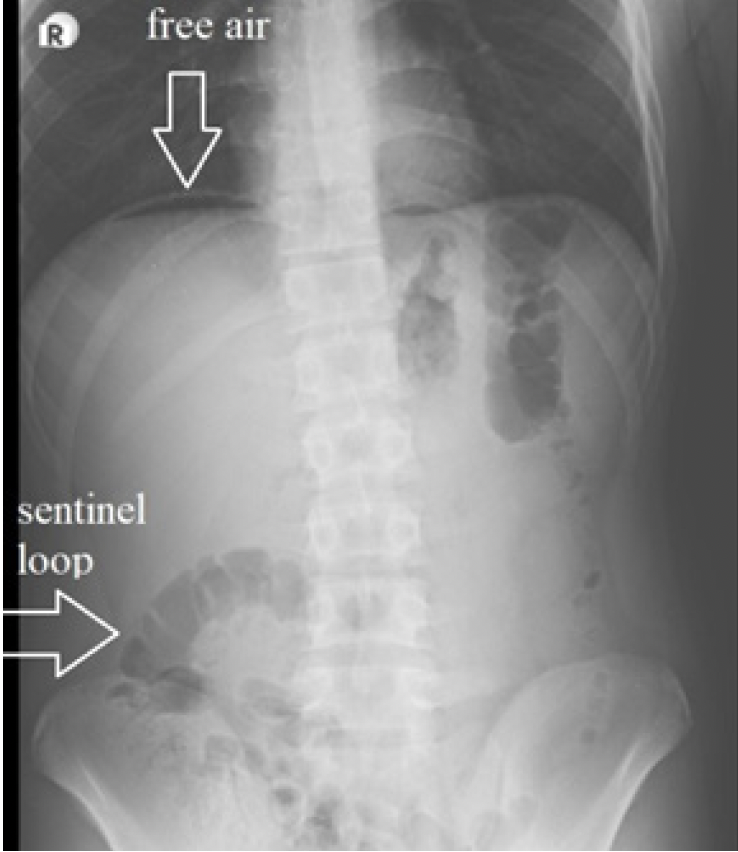

A total of 6 patients are enrolled in the study. All patients were males, and the median age of the patients was 16,65 years (range: 13-27 years ). All patients were admitted with abdominal pain lasting for no more than 4 days. Clinically, physical examination findings suggested acute appendicitis (tenderness/guarding/ rebound at the right lower quadrant) in all of the patients, and all underwent abdominal exploration for suspected acute appendicitis, but were finally concluded as Valentino’s Syndrome. In 1 patient with free air on plain X-ray examination (Figure 1), Valentino’s Syndrome was suspected before the operation and confirmed with laparoscopic exploration (Patient no:5). The duodenal perforation was possibly healed as no leak was observed after freeing the para-duodenal adhesions and air leak test was performed through the nasogastric tube. All patients had turbulent fluid in the pelvis and right paracolic gutter, but appendix vermiformis appeared as ‘innocent’ and was not perforated or inflamed enough to be the cause of turbulent fluid (Figure 2a-2d). Therefore, the attending surgeon urged to find the primary cause in all patients. Exploration of the whole abdomen was possible in 5 patients who underwent laparoscopic exploration but not in 1 patient who underwent open surgery. Periduodenal inflammation and omental adhesions were noticed in these patients (Figure 3a, 3b, 3c). When these adhesions were bluntly dissected, obvious duodenal perforation was visible in 2 patients (Figure 3d). The procedure was converted to open in these patients to repair the duodenal ulcer perforation. However, the adhesions on the duodenal wall were dense and dissection was challenging and regarded as hazardous in 3 patients, suggesting a chronic process and a possible healed perforation (Figure 3a and 3b). In the first case of these 3 patients, a simultaneous gastroscopy was performed during the operation, which demonstrated multiple duodenal ulcers, and integrity of the duodenal wall was confirmed (by air leak test and endoscopic vision). In the other 2 patients, a leak test was performed under laparoscopic vision by applying air through the NG tube. Appendectomy was performed in all these 3 patients due to the mystic nature of the condition, and the appendiceal lumen was found intact on histological examinations. No further action was performed, but all received medical treatment for duodenal ulcer until they had an elective gastroscopy. In 2 of these patients, intraperitoneal fluid was sampled intraoperatively for amylase and lipase levels with concomitant blood samples to compare with serum levels, and was found significantly higher. Intraperitoneal/serum amylase levels were 596/88 u/L and 150/59 U/L, lipase levels were 1551/29 U/L and 91/20 U/L. These findings are regarded as evidence of the duodenal origin of the intraperitoneal fluid. These 3 patients were subgroupped as Type B (occult, recovered, or healed duodenal perforation), and others were subgrouped as Type A (non-patent, disrupted duodenal wall).

All patients, except 2, denied any previous history of dyspeptic symptoms. All patients underwent plain X-ray examination in an erect position and ultrasonographic examination, but only 2 underwent computerized tomography (CT) with IV contrast before the operation. Suggestive findings of acute appendicitis on US examination were double wall thickness > 6mm (n = 4), increased mesenteric echogenicity at the right lower quadrant (n = 5), and right paracolic and/or pelvic fluid (n = 6). Suggestive findings of acute appendicitis on CT were double wall thickness > 6 mm (n = 1) and right paracolic and pelvic fluid (n = 1). In 1 patient (patient 5), free air under the diaphragm was noted in plain x-ray in the erect position (Figure 1), but no obvious open perforation was found when periduodenal inflamed tissues were dissected and regarded as Type b (Figure 3a and 3b). No free air was demonstrated in any of the plain X-rays or CT images except for this patient. All patients had physical examination findings suggestive of acute appendicitis (tenderness, guarding, and/or rebound localized to the right lower quadrant), and inflammatory markers were elevated in all (white blood cell count and C-reactive protein). Laparoscopic approach was performed in 5 patients but converted to open surgery in 2, at the discretion of the attending surgeon. One patient underwent open surgery but needed an additional separate open incision for repair of an open duodenal perforation. Intraoperative gastroscopy was performed in 1 patient to confirm the patency of the duodenal wall (patient 2). All patients underwent gastroscopy after the recovery period of the operation, and findings of bulbar duodenitis were present in all. Helicobacter pylori was confirmed histologically in 4 patients.

Figure 1. Subdiaphragmatic free air on the left side and sentinel loop in the right lower quadrant